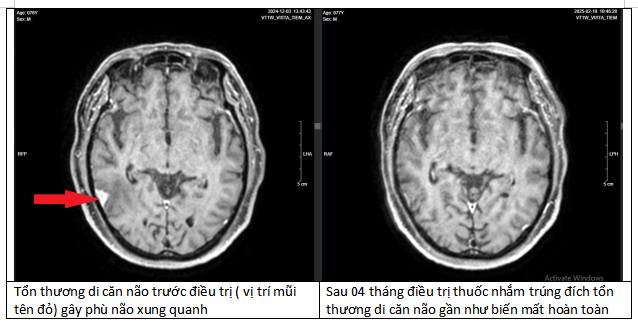

Kết quả MRI sọ não xuất hiện tổn thương nghi ngờ ác tính do di căn. Để tìm căn nguyên, bệnh nhân đã được tầm soát toàn cơ thể.

Sau 4 tháng điều trị, các khối u tại phổi, não, xương của bệnh nhân đều thu nhỏ lại. Đặc biệt tại phổi, khối u đã biến mất tới 90%. Đây là một kết quả kinh ngạc, tạo ra kỳ tích cho bệnh nhân.